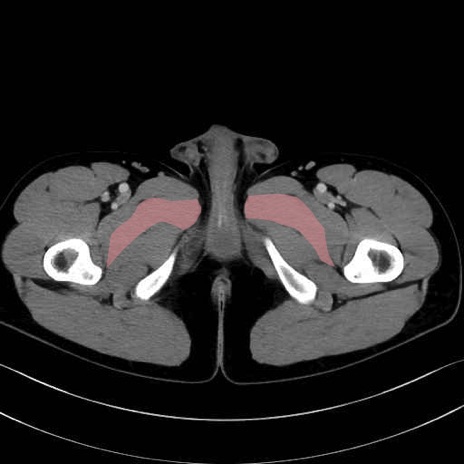

短内転筋(Adductor brevis) のCT画像の解剖

短内転筋 (Adductor brevis)